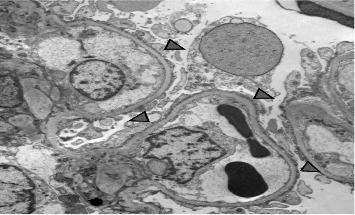

Proteinuria in a patient with long-standing Type 1 diabetes mellitus (T1DM) usually suggests diabetic kidney disease (DKD). However, DKD occurs late in the disease and is associated with hypertension and retinopathy. We report an adolescent with T1DM who, 1 year after initial diagnosis, developed nephrotic syndrome (NS). He was treated with steroids but developed frequent relapses and became steroid-dependent. A subsequent kidney biopsy revealed minimal change disease (MCD) and mild DKD. He was treated with mycophenolate mofetil (MMF) and remains in remission. Primary podocytopathy, such as MCD, is a rare cause of NS in a patient with T1DM. Indications for kidney biopsy and treatment options are similar to those of other children with a diagnosis of NS. This report highlights that, although rare, primary glomerulopathy can occur in pediatric diabetic patients and should be considered in the differential diagnosis of proteinuria, as early recognition and intervention can lead to favorable outcomes.

长期患有1型糖尿病(T1DM)的患者出现蛋白尿通常提示糖尿病肾病(DKD)。然而,DKD在疾病后期才会出现,且与高血压和视网膜病变有关。我们报告了一名患有T1DM的青少年,在初次诊断1年后出现了肾病综合征(NS)。他接受了类固醇治疗,但频繁复发并对类固醇产生了依赖。随后的肾脏活检显示为微小病变病(MCD)和轻度DKD。他接受了霉酚酸酯(MMF)治疗,目前仍处于缓解期。原发性足细胞病,如MCD,是T1DM患者发生NS的罕见原因。肾脏活检的指征和治疗选择与其他诊断为NS的儿童相似。本报告强调,虽然罕见,但原发性肾小球病可发生于儿童糖尿病患者中,在蛋白尿的鉴别诊断中应予以考虑,因为早期识别和干预可带来良好的预后。